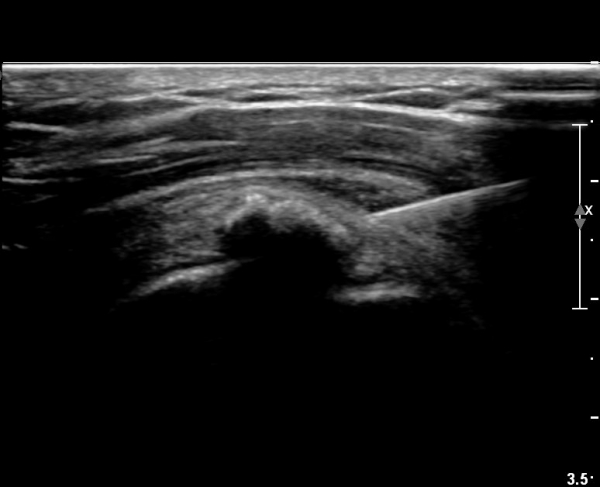

Á¡¾×³¶³» ÁÖ»ç ÈÄ ÁÖ»ç¹Ù´ÃÀ» ¹Ýº¹ÀûÀ¸·Î ´õ ÁøÀÔ½ÃÄÑ ¼®È¸¸¦ ºÐ¼âÇÑ´Ù(»çÁø 4).